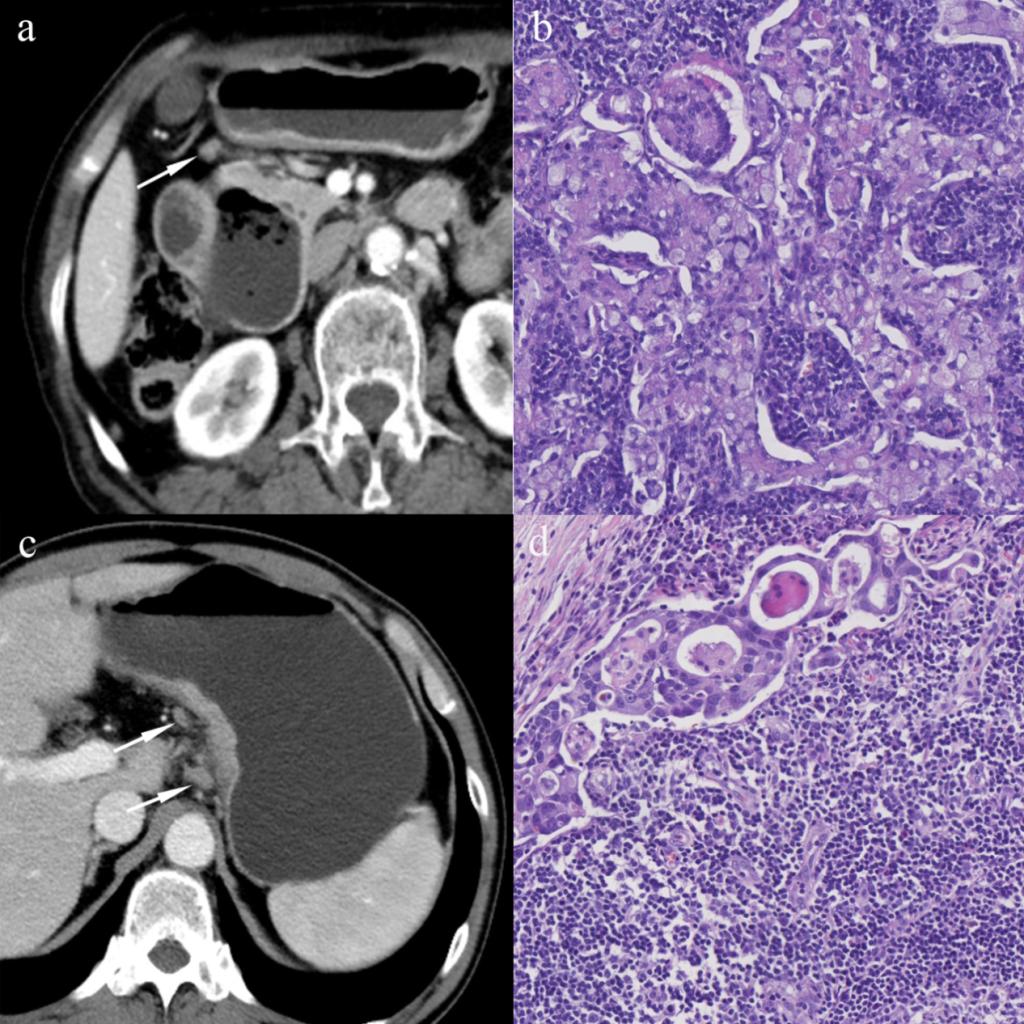

图1 区域淋巴结的CT及病理影像